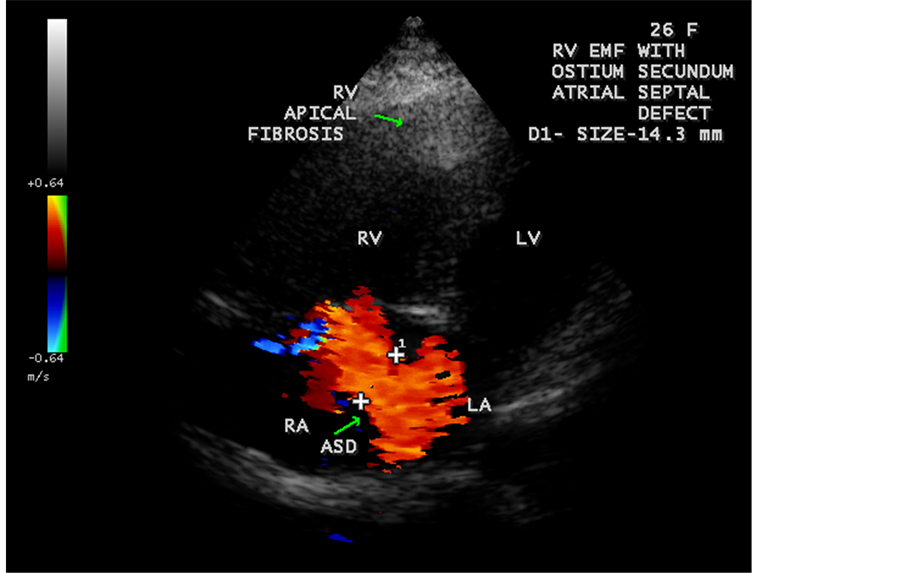

Figure 47. RV EMF with ostium secundum atrial septal defect (ASD) in a 26-year-old female antenatally (Primi with 9 months amenorrhea).

A left ventricular EMF mimicking apical left ventricular hypertrophic cardiomyopathy as shown in Figure 23, Figure 24 and Figure 25 in a 2-year-old male child and an apical right ventricular hypertrophic cardiomyopathy in a 60-year-old female as shown in Figure 26 mimicking as right ventricular EMF had been found by Transthoracic echocardiographic screening. A right ventricular EMF associated with Psoriasis was shown in Figure 3 to Figure 7 in a 52-year-old male and a left ventricular EMF associated with pemphigus skin lesion in a 63-year-old male as in Figure 40 were detected in this region of Thoothukudi. RV EMF associated with congenital heart diseases such as ostium secundum atrial septal defect in a 26-year-old female antenatally (Primi with 9 months amenorrhea) as shown in Figure 49 and Figure 64 to Figure 66 in a 9-year- old girl. RV EMF associated with RV outflow tract disease (“Double chambered right

ventricle”) in a 16-year-old female as shown in Figure 50 to Figure 53 were detected. RV EMF with rheumatic involvement of mitral valve as shown in Figure 54 and Figure 55 in a 44-year-old female and in Figure 63 in a 55-year old female. Biatrial enlargement due to rheumatic atrioventricular (AV) valves (mitral and tricuspid) involvement characterized by stenosis of the valves are illustrated in Figure 56 to Figure 59 in a 54-year-old female and it is differentiated from EMF which is characterized by AV valve regurgitation as shown in Figure 34 and Figure 60. RV EMF associated with thickening and fibrosis of moderator band in a 16-year-old female was shown in Figure 46. RV EMF associated with apical left ventricular hypertrophic cardiomyopathy was shown in a 47-year-old male as in Figure 61 and in a 65-year-old female as in Figure 62.